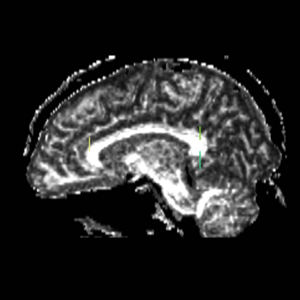

Cingulum

ROI 1) A coronal plane in the most anterior point of the corpus callosum was selected using the mid-saggital plane (Fig.18), and the left and right ROI1s were drawn on the superior side of the corpus callosum (Fig.15)

ROI 2) & ROI 3) The first coronal slice where the left and right corpus connect was selected: the left and right ROI2s were drawn on the superior side of the corpus and the left and right ROI3s were drawn on the inferior side of the corpus (Fig. 16 & 18)

Figure 18. Cingulum Bundle ROI's 1, 2, and 3